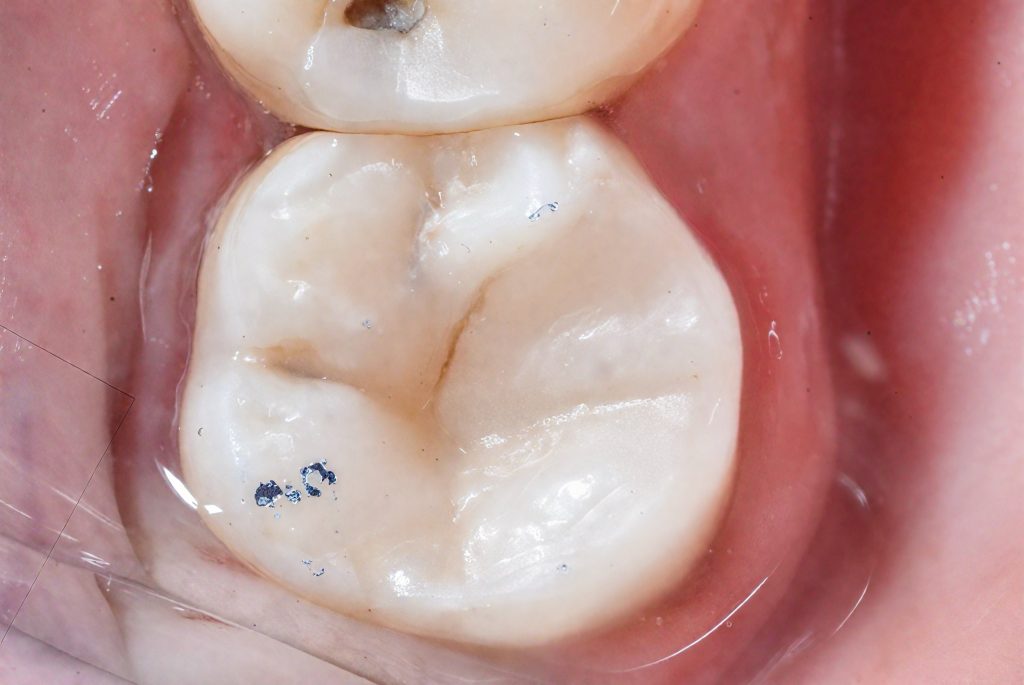

Selective enamel etching with 37 % phosphoric acid was followed by application of 8th-gen adhesive (BISCO).

Incremental anatomic layering was done with Tokuyama Estelite Sigma Quick, building primary and secondary anatomy under scope.

Cuspal coverage was performed biomimetically, ensuring ideal occlusal contact and stress distribution (Fig 8 & 9).

8️⃣ Occlusal final view – cuspal coverage

9️⃣ Polished final intra-oral result